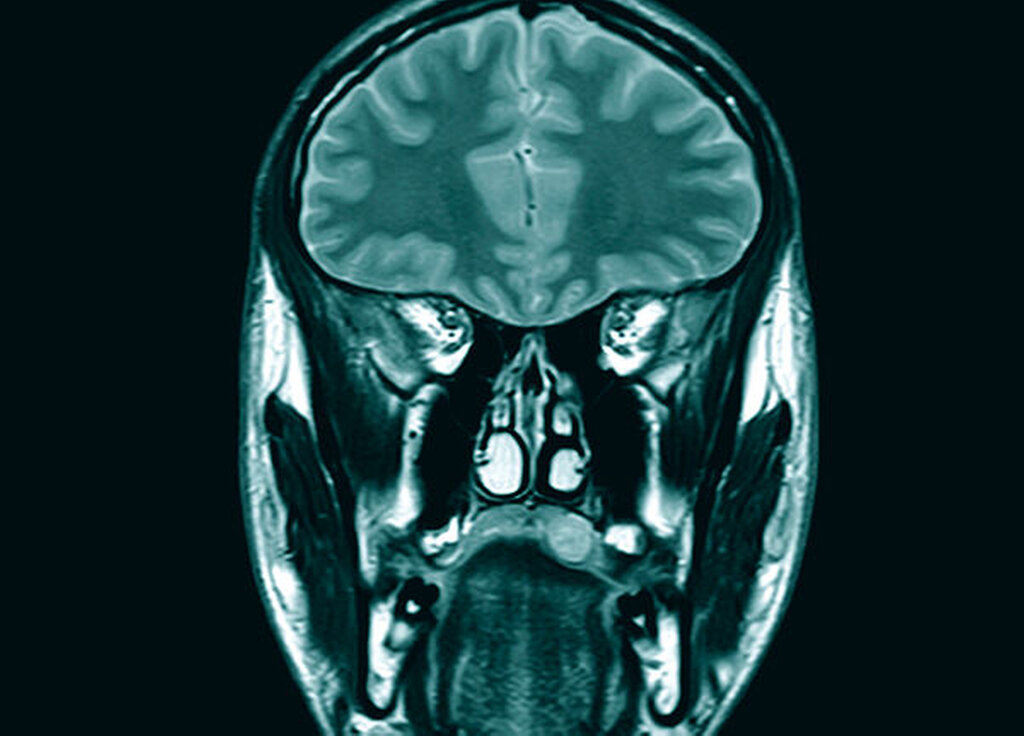

Zur weiteren Klärung der Dignität des Befunds waren sowohl eine bildgebende Untersuchung als auch eine histopathologische weitere Diagnostik indiziert. Aufgrund des Weichteilcharakters des Befunds erfolgte in einem ersten Schritt eine Magnetresonanztomografie des Mittelgesichts mit Kontrastmittel. Es zeigte sich eine homogen begrenzte, kontrastmittelaufnehmende Raumforderung im Übergang zwischen hartem und weichem Gaumen ohne Zeichen einer Infiltration der Umgebungsstrukturen mit einem sagittalen Durchmesser von circa 3 cm. In der Zusammenschau der klinischen und bildgebenden Befunde bestand der Verdacht auf das Vorliegen eines pleomorphen Adenoms. Aufgrund der geringen Größe des Befunds wurde zur histologischen Sicherung der Diagnose eine Resektion in toto angestrebt.

Die klinischen und bildgebenden Kontrollen (per MRT) blieben auch mehr als 24 Monate nach der Erstdiagnose ohne Anhalt für ein Rezidiv (Abbildungen 7 und 8).